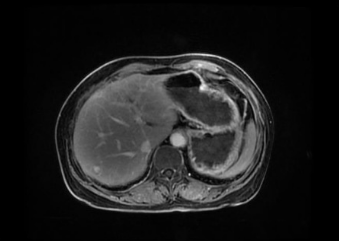

本次參賽病例為一例直腸神經(jīng)內(nèi)分泌癌伴肝轉(zhuǎn)移病灶的老年女性患者,影像科專家評(píng)估分期T3cN1M1,外科專家評(píng)估患者暫無(wú)手術(shù)指征,經(jīng)與腫瘤內(nèi)科專家和放療科專家行MDT會(huì)診后,予患者先行化療?;颊呋驒z測(cè)外送結(jié)果提示患者敏感性較高的化療藥物為:伊立替康和卡培他濱?;颊咝幸晾婵?FU+亞葉酸鈣+貝伐單抗治療4周期后,病情評(píng)估為穩(wěn)定,后患者至放療科行卡培他濱化療聯(lián)合直腸原發(fā)灶局部放療,直腸原發(fā)灶獲得影像學(xué)部分緩解。后患者出現(xiàn)腹主動(dòng)脈旁新發(fā)腫大淋巴結(jié)。再次行病理科、影像科、腫瘤內(nèi)科和放療科多學(xué)科協(xié)作診療,考慮患者為神經(jīng)內(nèi)分泌癌,根據(jù)2023歐洲神經(jīng)內(nèi)分泌腫瘤學(xué)會(huì)推薦轉(zhuǎn)移性消化系統(tǒng)NEC治療以順鉑聯(lián)合依托泊苷為主。并且神經(jīng)內(nèi)分泌癌2024 CSCO指南推薦對(duì)于既往接受過(guò)系統(tǒng)治療且持續(xù)進(jìn)展、缺乏標(biāo)準(zhǔn)治療的轉(zhuǎn)移性NEC患者,也可考慮免疫治療。因此,予患者行依托泊苷聯(lián)合順鉑治療,并且聯(lián)合索凡替尼和恩沃利單抗。兩周期用藥后復(fù)查示腹主動(dòng)脈旁新發(fā)腫大淋巴結(jié)較前明顯縮小,其余病灶穩(wěn)定。 初治時(shí) 直腸病灶放療后出現(xiàn)新發(fā)腹主動(dòng)脈淋巴結(jié) 治療后肝臟病灶穩(wěn)定,直腸原發(fā)灶和腹主動(dòng)脈腫大淋巴結(jié)明顯縮小 王明 主任醫(yī)師 乳腺與腹部腫瘤放療科(放療一科)主任 專業(yè)擅長(zhǎng):各種胸部腫瘤:如乳腺癌、食管癌的放化療、免疫、靶向治療,以及各種腹部腫瘤的放化療,尤其擅長(zhǎng)各種消化道腫瘤:胃癌、肝癌、膽管癌、胰腺癌、結(jié)直腸癌的放療、化療、靶向等綜合治療。泌尿系腫瘤:腎癌、膀胱癌、前列腺癌等腫瘤的綜合治療。 張一擎 主治醫(yī)師 滄州市中心醫(yī)院乳腺與腹部腫瘤放療科(放療一科) 苗玉 副主任醫(yī)師 滄州市中心醫(yī)院病理科 專業(yè)擅長(zhǎng):消化系統(tǒng)腫瘤及消化道早癌篩查病理診斷。 孫敏 副主任醫(yī)師 磁共振成像科 從事臨床工作十多年,對(duì)臨床常見(jiàn)疾病的核磁診斷有豐富的經(jīng)驗(yàn)。 李哲 副主任醫(yī)師 滄州市中心醫(yī)院腫瘤內(nèi)一科 楊立勝 主治醫(yī)師 滄州市中心醫(yī)院結(jié)直腸肛門外科 專業(yè)擅長(zhǎng):結(jié)直腸癌、肛周常見(jiàn)疾病、盆底疾病的外科診療。